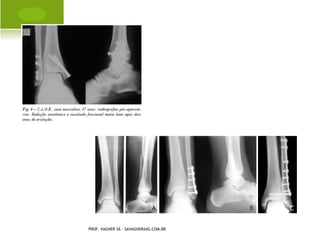

E PIFISIÓLISE    CABEÇA

FEMORAL

   Epifisiolistese

   Coxa-vara do

adolescente

   Coxa vara

epifisária

PROF. VAGNER SÁ - SAVAGNER@IG.COM.BR

CLASSIFICAÇÃO

T RATAMENTO CIRÚRGICO